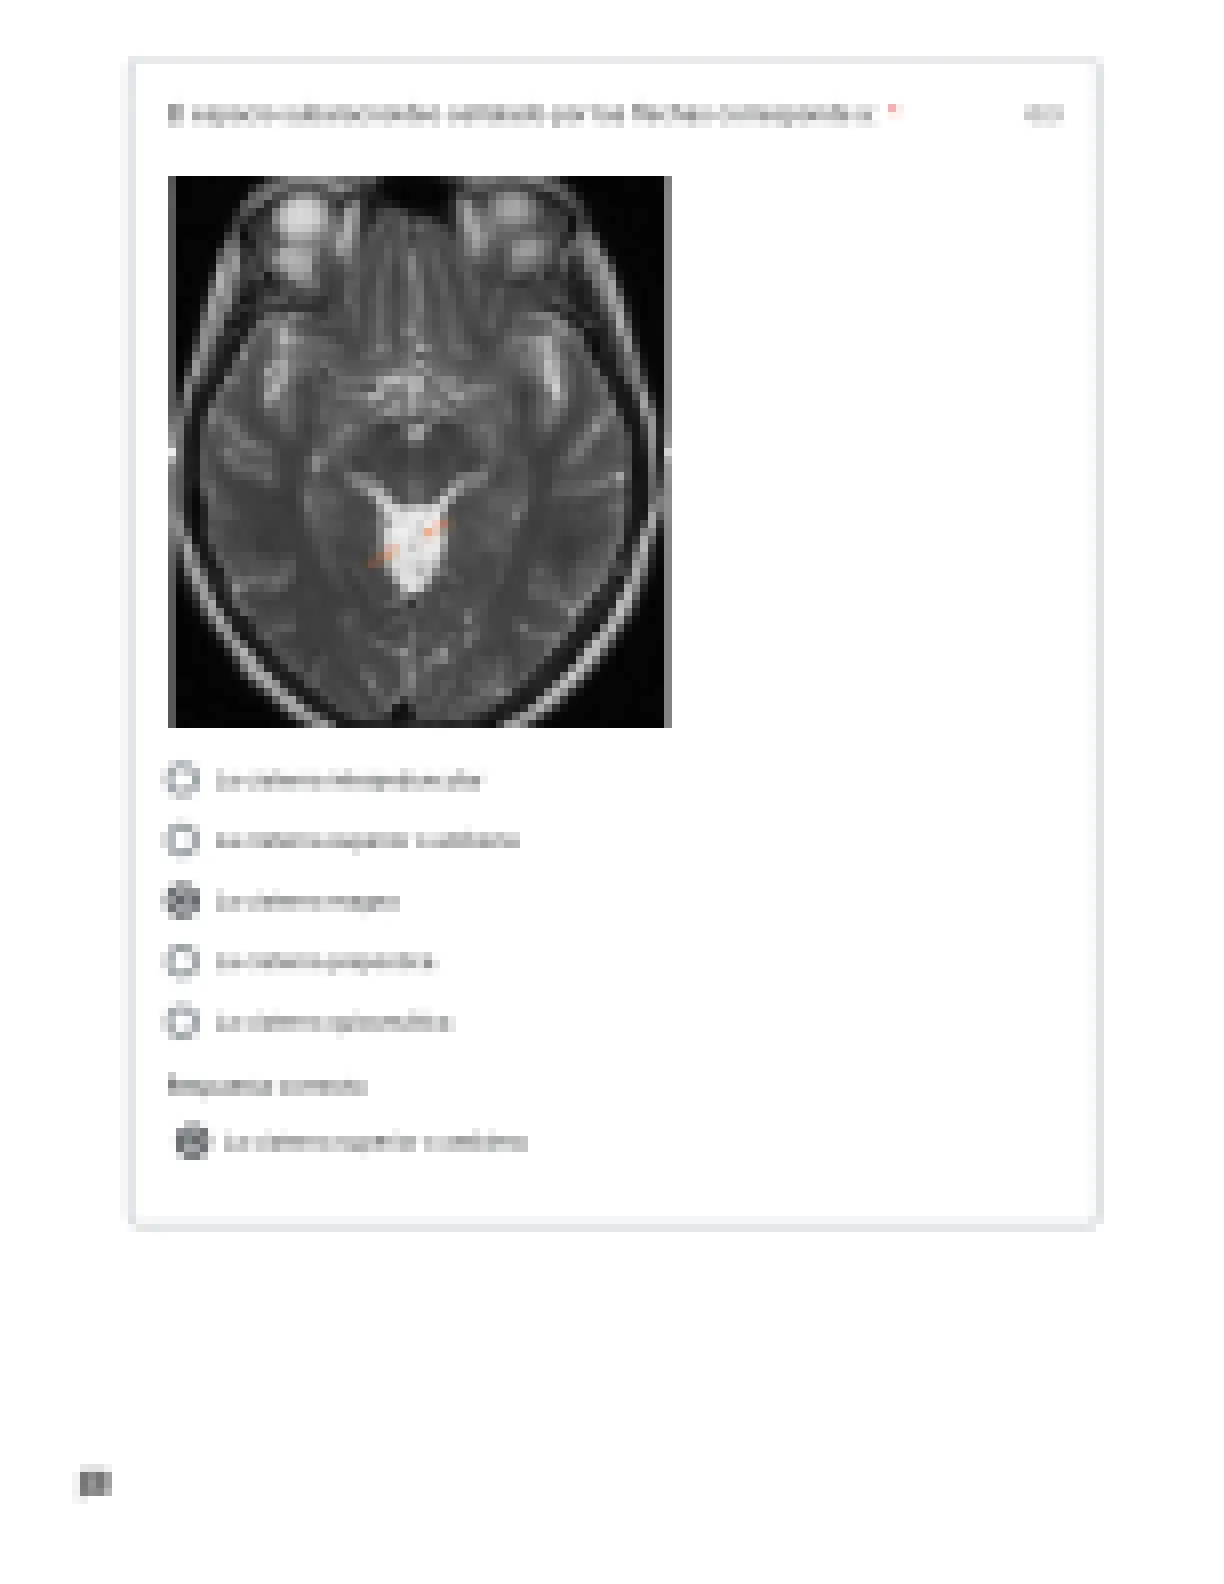

2017979 - ANATOMIA 1

Examen neuroanatomia I